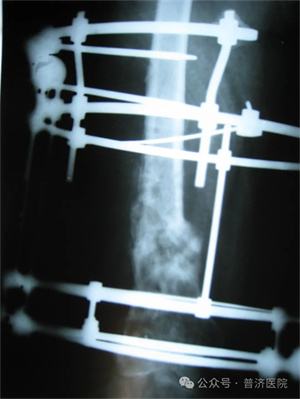

科室开展特色微创治疗:微创治疗拇外翻( 大脚骨 ),椎间孔镜( 治疗腰椎间盘突出 ),膝关节镜( 治疗膝关节疾病 ),伊利扎洛夫技术治疗骨折、骨不连、骨髓炎、肢体畸形。骨膜牵张术治疗糖尿病足。经皮椎体成形术治疗胸腰椎压缩骨折、病理骨折、椎体血管瘤等、中医微创治疗治疗各种软组织手术疾病。中西医相结合治疗骨折。